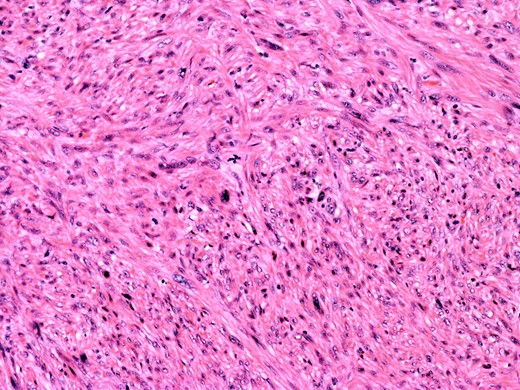

At the time of referral, the lesion had dramatically increased in size and become more symptomatic, therefore surgical excision was agreed. He underwent a trans-scrotal right epididymectomy where an irregular white mass measuring 15 × 46 × 35 mm3 was excised. Histological examination demonstrated a well delineated mass comprising fascicles of cytologically malignant spindle cells (Fig. 2). These showed moderate to nuclear pleomorphism, frequent mitotic figures, including atypical forms, and zones of coagulative necrosis (Fig. 3). Immunohistochemistry showed the tumour cells were strongly and diffusely positive for desmin, smooth muscle actin and h-caldesmon. FISH analysis for MDM2 amplification excluded a dedifferentiated liposarcoma, the main differential diagnosis at this site. Overall, the features were those of a paratesticular LMS, which was FNCLCC/Trojani grade 2.

The tumour comprises fascicles of atypical spindle cells showing prominent cytological atypia and nuclear pleomorphism. Zones of coagulative tumour cell necrosis are present.

On higher power, severe cytological atypia is evident, with frequent mitotic figures including atypical mitotic forms.